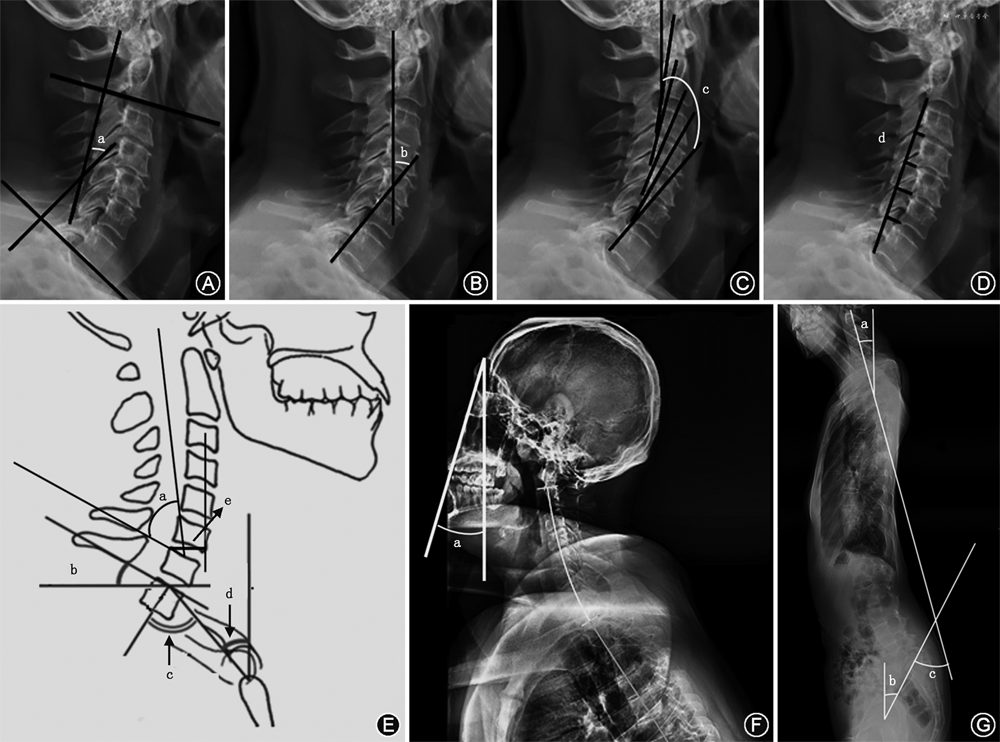

1.CL的测量:测量CL的4种最常见方法包括改良的Cobb方法(mCM)、Jackson生理应力线(JPS)、Harrison后切线(HPT)方法和Ishihara指数[6](图1A~D)。通过C2法的mCM来获得CL,沿C2和C7下终板绘制两条水平线,分别绘制与前两条线垂直的附加线,两条垂直线所成的角度即C2-7 CL;C1法是从C1的前结节延伸到C1棘突的后缘代替C2的终板作为上参考线来测量C1-7颈椎矢状位Cobb角;用JPS法测量CL时沿C2和C7椎体后壁各画一条直线,这两条直线交角的数值就是CL的测量值。HPT法是从C2到C7所有的颈椎椎体后表面画出平行的直线,然后将所有的节段角度相加得到一个整体的CL角度[7]。Ishihara指数,又称颈椎曲度指数,连接C2的椎体下后端到C7的椎体下后端,从C3、C4、C5、C6椎体下后端分别做垂线,Ishihara指数为4条垂线段的长度和除以C2下后端到C7下后端连线的长度。美国的Janusz等[8]通过对44例患者mCM、JPT和HPT方法的CL测量,认为三种方法均可靠有效,且不同测量者的测量值无明显差异。

矢状面轴向距离(SVA)可以评估全脊柱整体矢状位平衡,颈椎矢状位平衡可以通过CSVA来评估。C2-7 SVA是过C2椎体中心的铅垂线到C7椎体上终板后端之间的距离(图1E)。头部重心(CGH)-C7 SVA(CGH-C7 SVA)是过外耳道前缘的铅垂线到C7椎体后上角的垂线间距离[8]。Iyer等[10]通过双平面成像系统报告了120例无症状患者的C2-7 SVA平均值为21.3 mm,赵文奎等[13]对132名中国无症状成年人测量C2-7 SVA为(18.67±7.96)mm,CGH-C7 SVA为(22.95±12.18)mm。

T1倾斜角是T1椎体上终板的延长线与水平线之间的夹角(图1E),T1倾斜角和CL的关系类似于骨盆投射角(PI)和腰椎前凸角(LL)的关系,因为更大的T1倾斜角需要更大的CL来平衡胸部入口和头部的重量。当T1倾斜角在13°~25°时,机体为保持视线水平,可通过上颈椎过伸过屈代偿颈椎的潜在失衡;当T1倾斜角>25°时,颈椎整体容易前倾,重心前移,在重力的作用下,CSVA增大,颈椎曲度发生后凸趋势,导致颈椎矢状位失衡;当T1倾斜角<13°时,存在负平衡[14]。

TIA是T1椎体上终板中点到胸骨上缘连线和T1椎体上终板垂线之间的夹角(图1E),Lee等[11]认为胸骨、T1肋骨和T1椎体的固定连接导致胸廓入口相对固定,因此,TIA是一个固定的形态学参数。颈部倾斜角是T1椎体上终板中点到胸骨上缘连线与垂直线的夹角(图1E),在无症状的人群中颈部倾斜角保持在44°左右。TIA在数值上等于T1倾斜角和颈部倾斜角相加之和,可以推测较大TIA者为消耗最小能量而获得颈椎水平注视和矢状排列,则需要相应更大的T1倾斜角,进一步CL相应增加[11]。